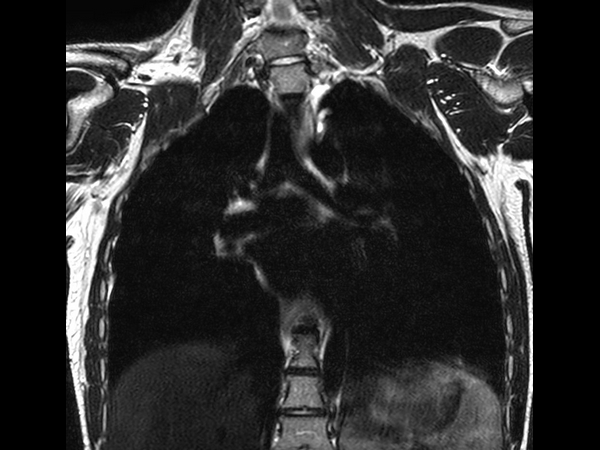

T2w SPIR - MultiVane XD